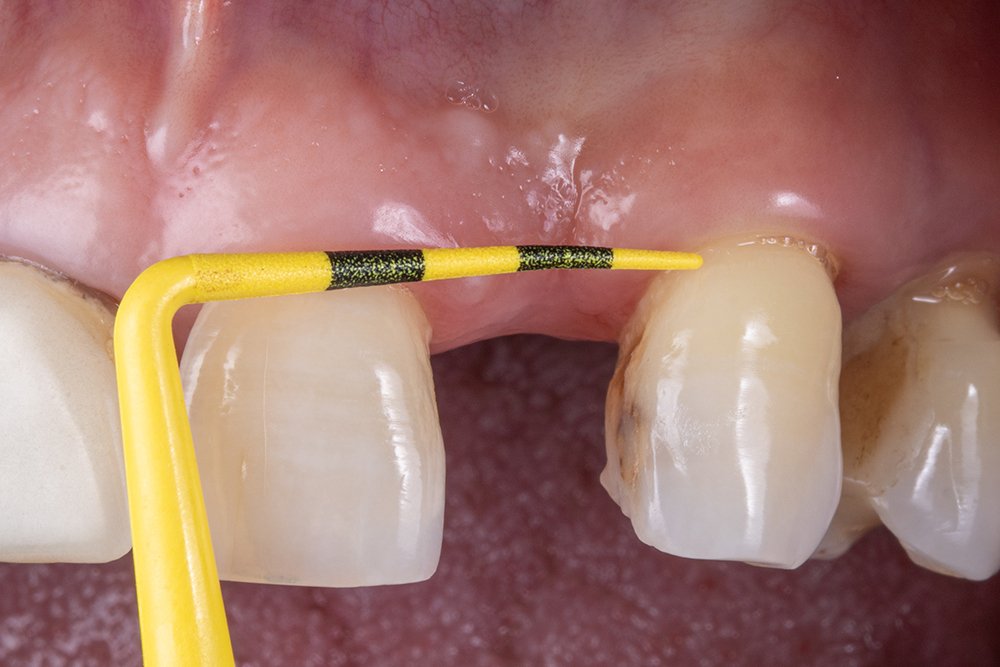

Neste caso clínico, nota-se ao exame inicial a perda do elemento 22. Logo, a colocação do implante se encontra em uma situação tardia, segundo a classificação de Chen et al. (2009). Ao mensurar o espaço para reabilitação através da sonda Colorvue, notou-se um espaço favorável para instalação do implante e uma boa faixa de tecido queratinizado, eliminando a técnica de enxerto de tecido conjuntivo para aumento de espessura tecidual.